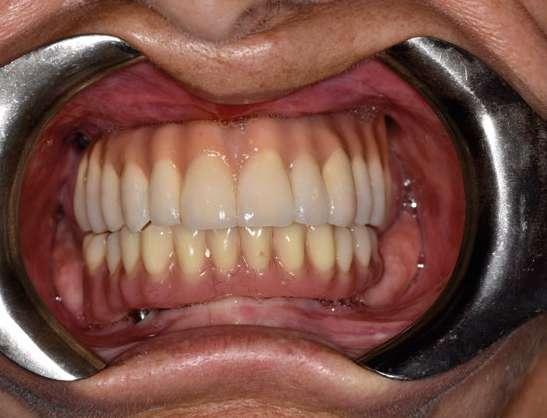

Figuras 3-6. Imágenes de un caso de prótesis atornillada en molar unitario inferior. Vemos el estado de los tejidos blandos gingivales tras la segunda fase y colocación del transepitelial unitario y la radiografía. En las imágenes inferiores (5 y 6) observamos el caso a los 4 años y 10 años de seguimiento, con estabilidad completa de los tejidos óseos peri-implantarios.

Figuras 7-10. En las dos imágenes superiores (7 y 8) observamos la realización de la prótesis cementada mediante un bioplilar fresado a la altura gingival con la radiografía antes del cementado de la corona. En las imágenes inferiores (9 y 10) vemos la prótesis a los 7 años de seguimiento y a los 9 años transformada en una prótesis atornillada al perderse la pieza anterior al implante y realizarse un puente con el nuevo implante. En este caso, el nivel óseo permanece estable con el paso del tiempo.